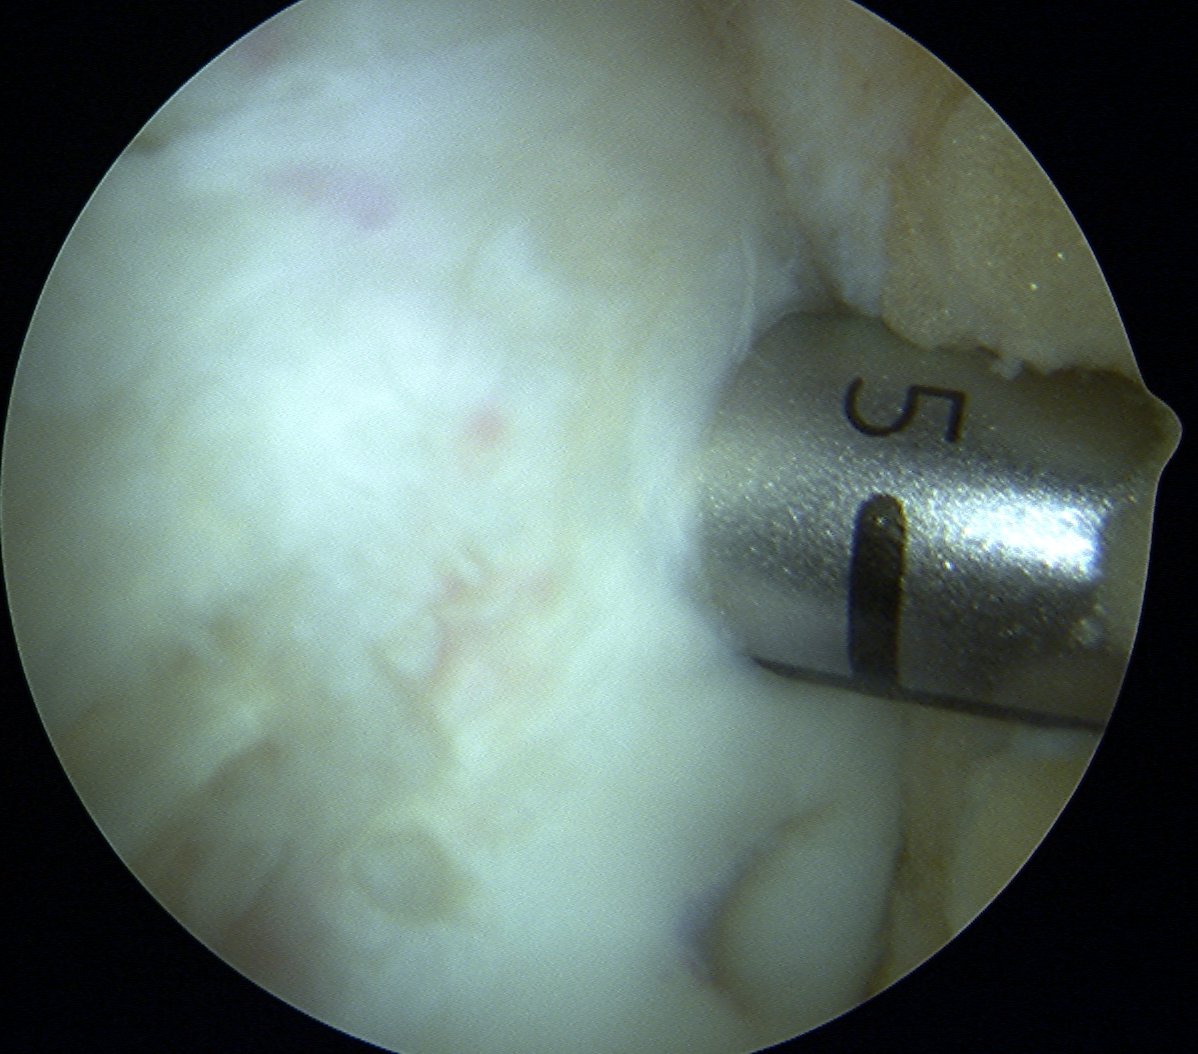

Drill site of mosaicplasty with 4.5 mm drill

- overdrill 2 - 4 mm

Insert dilator

Insertion device

- place over drill hole